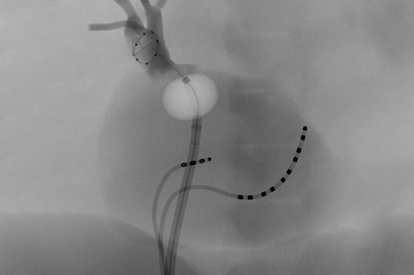

EVAR (Endovascular Aneurysm Repair) Module